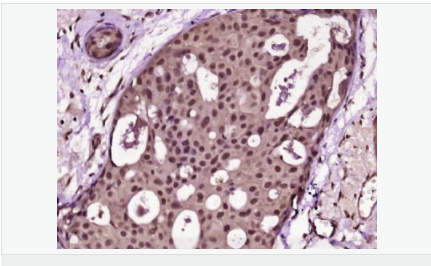

| 產(chǎn)品介紹 | Proliferation Marker Ki67 antigen is the prototypic cell cycle related nuclear protein, expressed by proliferating cells in all phases of the active cell cycle (G1, S, G2 and M phase). It is absent in resting (G0) cells. Ki67 antibodies are useful in establishing the cell growing fraction in neoplasms (immunohistochemically quantified by determining the number of Ki67 positive cells among the total number of resting cells = Ki67 index). In neoplastic tissues the prognostic value is comparable to the tritiated thymidine labelling index. The correlation between low Ki67 index and histologically low grade tumours is strong. Ki67 is routinely used as a neuronal marker of cell cycling and proliferation. Function: Thought to be required for maintaining cell proliferation. Subcellular Location: Nucleus. Chromosome. Predominantly localized in the G1 phase in the perinucleolar region, in the later phases it is also detected throughout the nuclear interior, being predominantly localized in the nuclear matrix. In mitosis, it is present on all chromosomes. Similarity: Contains 1 FHA domain. SWISS: P46013 Gene ID: 4288 Database links: Entrez Gene: 4288 Human Entrez Gene: 17345 Mouse Omim: 176741 Human SwissProt: P46013 Human SwissProt: Q91VE6 Mouse Unigene: 689823 Human Unigene: 80976 Human Unigene: 4078 Mouse Unigene: 233802 Rat Important Note: This product as supplied is intended for research use only, not for use in human, therapeutic or diagnostic applications. 細胞增殖標志物(Proliferation Marker) Ki67與PCNA一樣,為細胞增殖的一種標記,在細胞凋亡中S、G2 、M期均有表達,G0期缺如。 Ki-67增殖指數高低與許多腫瘤的分化程度、浸潤、轉移以及預后密切相關(guān),因此被廣泛作為各種惡性腫瘤的必檢項目之一。 |